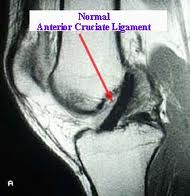

The ACL, or anterior cruciate ligament, is one of four stabilizing ligaments of the knee. It is located within the knee joint and when torn, can leave the patient with the inability to perform activities that require cutting, pivoting, and a change of direction. Heavy lifting, climbing, and other job activities can be difficult as well. Walking, swimming, and other straight ahead and low impact activities are less often affected by this injury. ACL tears primarily occur via noncontact mechanisms. That is, an athlete will often be changing direction or landing when the injury occurs. These moments can be quite painful and patients will often feel or hear a pop, followed by rapid swelling of the knee and the inability to bear weight on the leg.

Most ACL tears will have the typical history above. I recommend anyone with that history to be evaluated by a physician in short time. That evaluation will focus on several things. First the stability of the knee will be tested on physical examination. This can also diagnose other ligament tears that can be associated with ACL tears. X-rays are helpful to rule out other injuries as well. Commonly this evaluation will result in an MRI, or magnetic resonance image, being ordered. This test, which does not involve radiation, will evaluate the soft tissue, cartilage, and bone of the knee with higher detail than an x-ray. When this information is available, your physician will be able to provide a complete diagnosis and treatment plan.